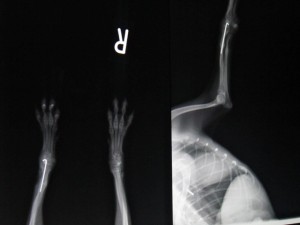

1か月後のレントゲンです。

骨化も順調ですので抜ピンを行いました。